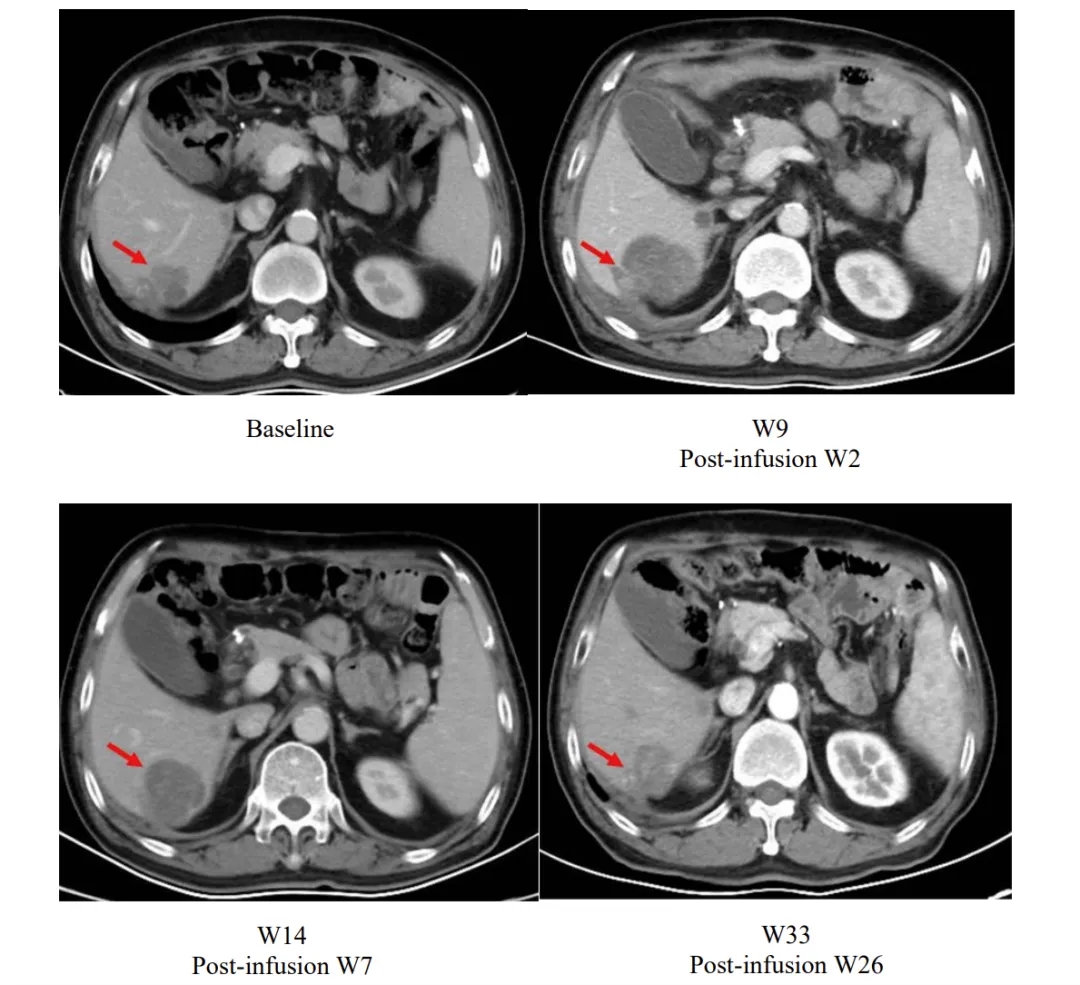

其中一个典型案例引发广泛关注:患者输注satri-cel后第2周肝脏病灶虽较基线增大,但后续随访中持续缩小,至第26周已小于基线水平,直观印证了该疗法的持续抗肿瘤活性。

▲图源“The Lancet”,版权归原作者所有,如无意中侵犯了知识产权,请联系我们删除